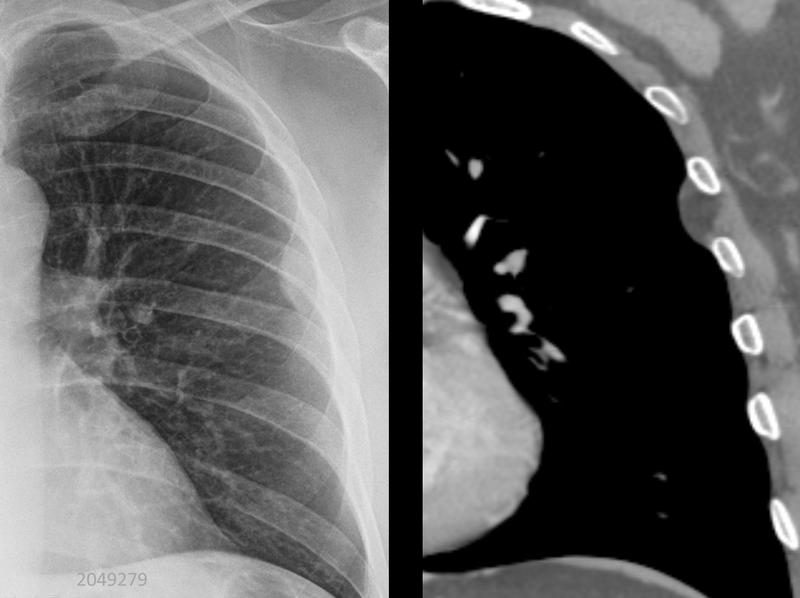

Gallery Pleural pleural lipoma

pleural lipoma